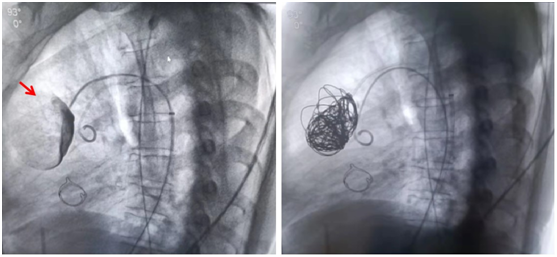

術(shù)中造影顯示動(dòng)脈瘤(箭頭所示),用彈簧圈填塞

術(shù)后造影顯示瘤體內(nèi)無造影劑外溢